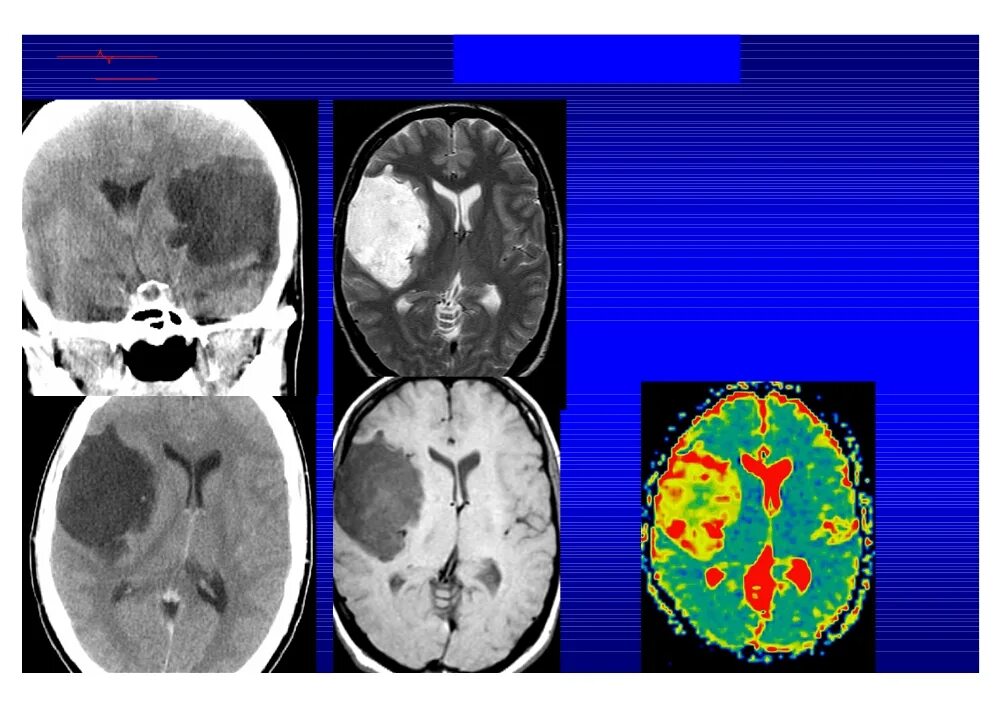

Мрт височных костей в режиме dwi